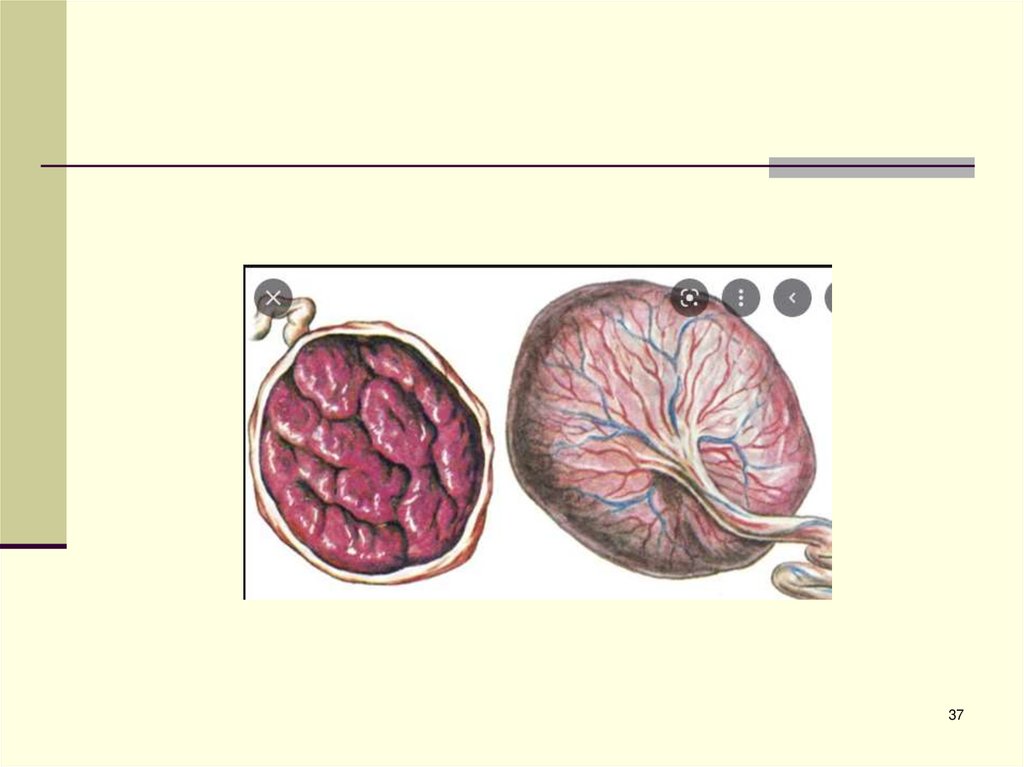

48. ПЛОДНАЯ ЧАСТЬ ПЛАЦЕНТЫ (Препарат)

49. МАТЕРИНСКАЯ ЧАСТЬ ПЛАЦЕНТЫ (Препарат)